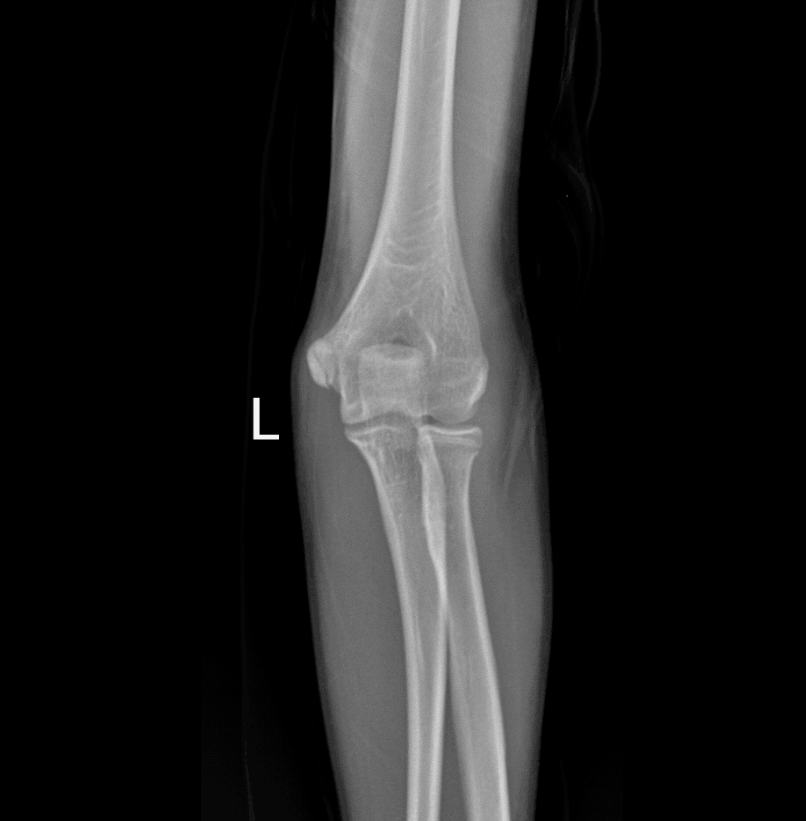

男,14岁,左肘关节外伤,大家看看。

左侧肘关节未见明显骨折征像,八字征阴性。

箭头所指为尺骨鹰嘴骨骺——鹰嘴骨与尺骨干的接合,男性在15~19岁、女性在13~14岁完成。

箭头所指考虑血管沟?

左肘关节侧位像:尺骨近端髓腔内似见低密度影。建议结合临床,必要时CT检查。